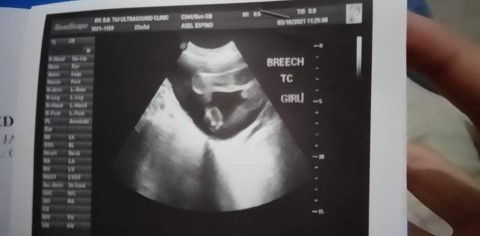

me po ☺️ EDD: FIRST WEEK OF JULY ♥️♥️♥️